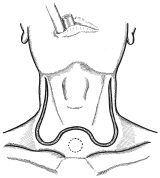

器械吻合器を用いた、咽頭部食道癌摘出後再建法

首の解剖の本と首っ引きで描きました。